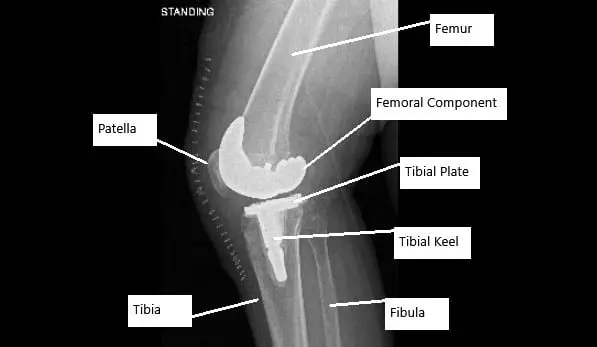

X-ray showing total knee replacement surgery in a patient with AVN knee.

- Stage 4: Severe osteoarthritis with significant joint destruction. The knee’s range of motion is severely limited, and total knee replacement may be necessary.

- Stage 3 & 4: In advanced stages, total knee replacement (TKR) surgery is the most effective treatment, providing relief from pain and restoring knee function.

- Total Knee Replacement: In severe cases, when the joint is extensively damaged, knee replacement surgery may be required. This procedure involves removing the damaged bone and cartilage and replacing them with artificial components.

Recovery and What to Expect After Treatment